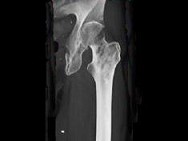

- 单项选择题患者50岁,可能性最小的诊断是 ( )

A、骨纤维结构不良

B、转移瘤

C、软骨肉瘤

D、骨髓瘤

E、以上都不是